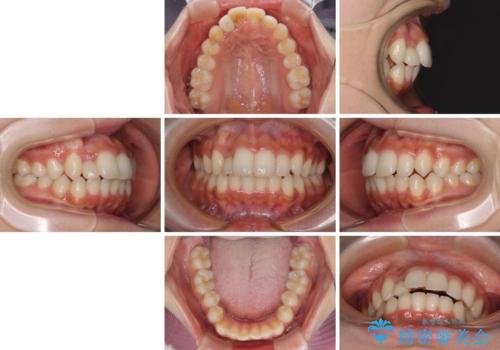

- 上下前歯のデコボコを気にして来院された患者様です。

前歯のセラミックが装着されている歯は、歯根が短くなっており、他院では抜けてしまうので矯正はできないと言われていたようです。

患者様と相談し、抜けてしまった場合にはインプラントあるいはブリッジによる補綴治療が必要となることを確認し、極力歯根に負担のかからないような仕上がりで治療を進めて行くこととしました。

デコボコを解消には、IPR(歯と歯の間を削る)をメインに歯列排列を設計し、インビザラインにて矯正治療を行うこととしました。

レントゲン写真上では、矯正治療前後で歯根長さに大きな違いはなく、抜歯を回避することができました。

上顎内側に転位している前から2番目の歯は移動が難しく、無理矢理歯根全体を動かそうと設計すると、歯肉退縮・歯髄壊死・歯根吸収といった危険性が増すため、無難なゴールにて治療を終えることとなりました。